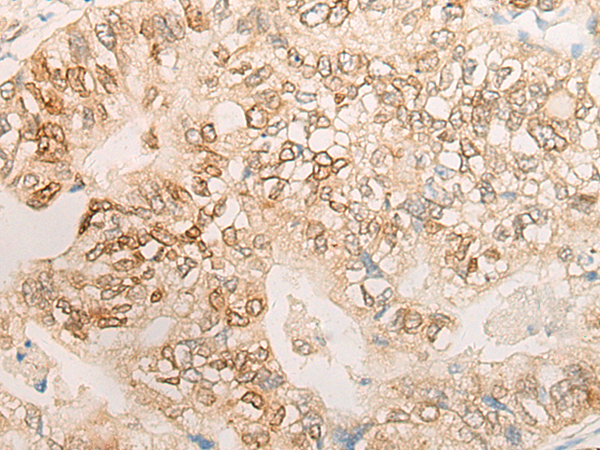

分类: 科研抗体货号: P13262别名: DMN; SYN应用: IHC反应种属: Human

分类: 科研抗体货号: P13239别名:应用: IHC反应种属: Human

分类: 科研抗体货号: P13219别名: CDP; CUX; p75; CASP; CDP1; COY1; Clox; p100; p110; p200; CUTL1; GOLIM6; CDP/Cut; Cux/CDP; Nbla10317应用: IHC反应种属: Human, Mouse, Rat

分类: 科研抗体货号: P13261别名: DSC; DSC1; DSC2; DSC4; CDHF3; HT-CP应用: IHC反应种属: Human, Mouse

分类: 科研抗体货号: P13237别名: DPR1; FRODO; HDPR1; DAPPER; THYEX3; DAPPER1应用: IHC反应种属: Human, Mouse

分类: 科研抗体货号: P13218别名:应用: IHC反应种属: Human

分类: 科研抗体货号: P13257别名: A4; MAM; DMDA; SCG3; 35DAG; DAGA4; DMDA1; LGMD2C; LGMDR5; SCARMD2; gamma-SG应用: WB,IHC反应种属: Human, Mouse

分类: 科研抗体货号: P13236别名: NSDDR; C11orf11; DAGLALPHA; DAGL(ALPHA)应用: IHC反应种属: Human, Mouse, Rat

分类: 科研抗体货号: P13217别名: ARP; AEGL1; HUMARP; CRISP-1; HEL-S-57; HSCRISP1D; HSCRISP1G应用: IHC反应种属: Human

分类: 科研抗体货号: P13256别名: GT24; NPRAP应用: IHC反应种属: Human, Mouse